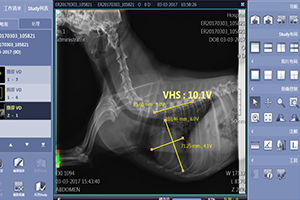

锥体测量系统测量犬猫心脏大小

Vertebral Scale System(VSS) to measure Canine and Feline Heart Size

1、锥体心脏比分(VHS)

椎体测量系统(Vertebral Scale System,VSS)研究的重点在于心脏大小和椎体长度的比较。该系统将心脏的长、短轴用从第4胸椎开始的椎体长度表示,其结果表示为椎体心脏比分(Vertebral Heart Size,VHS)。

2、VHS的测量

T-气管

L-心脏长轴,从气管分叉处腹侧至心尖的距离

S-心脏短轴,从心后缘与后腔静脉相交处的中点引长轴的垂线至心前缘的距离

L和S以从T4开始的椎体长度表示(估计至0.1 v),相加即为VHS。

VHS=L+S

如图所示,L=5.8v,S=4.6v,VHS=L+S=10.4v。

3、X线片的实际测量

如上图,VHS=5.7v+4.5v=10.2v

4、实际临床病例

这是一只京巴犬,因为剧烈咳嗽而就诊,经检查确诊为心衰。

如上图,VHS=5.6v+5.9v=11.5v

5、小结

侧位影像的VHS是评估犬心脏的较敏感指标,受胸廓形态、性别、年龄、摆位和评估者的经验影响较小,其正常范围具有品种特异性,是一种客观的、简单易用的评估方法。

正常范围——犬:VHS=9.7±0.5 v。猫:VHS <8v。